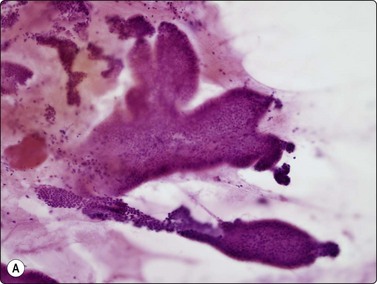

Islet cell tumours (Figs 11.18-11.20)

image image

Fig. 11.18 Islet cell tumor

(A) Poorly cohesive sheets and dispersal; cells with oval nuclei, stippled chromatin and small nucleoli (Pap, IP); (B) Mainly dispersed cells with uniformly round nuclei, speckled chromatin, moderate anisokaryosis; delicate cytoplasm; a suggestion of pseudorosettes (MGG, HP).

image

Fig. 11.19 Islet cell tumor

Tissue section corresponding to Figure 11.18 showing a trabecular and solid pattern (H&E, IP).

Fig. 11.20 Malignant islet cell tumor

Poorly cohesive cells of endocrine appearance; no obvious cytologic features to suggest malignancy. This tumor metastasized to the liver (MGG, HP).

Criteria for diagnosis

Many single and loosely grouped cells, pseudorosettes,

Rounded monotonous nuclei, mild to moderate anisokaryosis,

Speckled chromatin and 1–3 small nucleoli,

Poorly defined, finely granular cytoplasm, often dispersed in the background,

Nuclei eccentric if cytoplasm intact.

These functional or nonfunctioning tumors of adults are situated mainly in the body and tail of the pancreas. The tumors are well within the scope of EUS cytodiagnosis.114,115 The neoplastic cells are mainly dissociated, but often form loose acinar or follicular clusters and curved or circular rows (Fig. 11.18). In the majority of cases, nuclei are characteristically round to oval and uniformly small. Occasionally, nuclear anisokaryosis may be prominent, but the nuclear chromatin pattern varies little between cells. The chromatin is evenly distributed, coarsely granular or ‘speckled’. The small nucleoli are not easily seen in Giemsa-stained smears. Due to its fragility, the cytoplasm is often dispersed in the background. When it is preserved, nuclei are eccentrically situated within defined cell borders. A very fine, red granularity is often discernible in MGG smears with high magnification. Clumps of amyloid may occasionally be seen, but necrosis is not observed.113,116-119 The cytological pattern of most islet cell tumors is sufficiently characteristic to be easily distinguished from that of pancreatic adenocarcinoma. Production and secretion of specific hormone products cannot be distinguished on the basis of routine cytological smears alone. If the secretory products of the neoplastic cells can be identified by immunocytochemical methods, a more specific diagnosis can be made with confidence. General neuroendocrine markers will usually be positive, such as neuron-specific enolase, synaptophysin, chromogranin-A, PGP9.5 and CD56. Specific secretory products, e.g. insulin can be marked by appropriate antibodies but this does not necessarily correlate with raised serum levels. Electron microscopy will demonstrate dense-core neurosecretory granules. A decision on whether a tumor is benign or malignant is problematic. Even histopathology is poorly predictive of aggressive behavior. In general, nuclear atypia and pleomorphism cannot be relied on as cytological criteria of malignancy (Fig. 11.20). More aggressive behavior correlates with a raised proliferation index assessed using Ki-67 immunohistochemistry (> 2%).120 This is a parameter in the WHO 2004 histology based-grading system.121,122 Only documentation of metastasis finally provides proof of malignancy.123,124